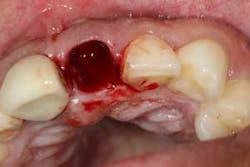

Although the literature varies as to the amount of bone volume that can be created/preserved, what material to use, as well as the indications for these procedures, (4) the majority of these studies agree that socket debridement is essential post-tooth extraction to ensure a good result. Socket debridement is particularly important when acute/chronic infections are present and cystic material lines the alveolar socket and/or tooth (figures 1 and 2). The complete removal of this infected tissue (figure 3) is tantamount to good bone fill, and can be the source of bone-graft contamination and infection.

After removal of the tooth, there are many methods of debriding the socket and various instrumentation that one can use. This author chooses to use a spoon excavator or spoon curette with serrations as a means of performing mechanical debridement (figure 4). After mechanical debridement, copious saline is used to irrigate the socket (figure 5), followed by the placement of cotton pellets soaked with either tetracycline (50 mg/ml) or 60% citric acid into the socket. After chemical modification, the socket is again irrigated and flushed with saline.